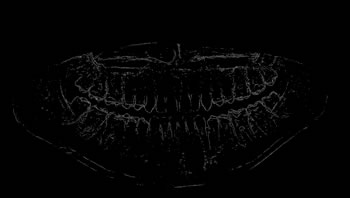

Refer to caption

Figure 6: Obtaining the values of the metrics used over each image of the data set.

Only the image ROIs were considered to calculate the metrics for the evaluation of the segmentation methods. The process presented in Figure 6 was carried out on all the segmented images obtained by each one of the 10 segmentation methods analyzed. Figure 7 illustrates the steps of the performance evaluation over 10 segmentation methods (see also Table 9 for a list of the evaluated methods).